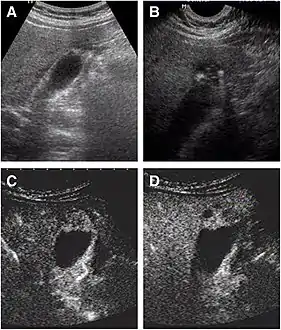

Abdominal ultrasound has low accuracy in differentiating gall bladder adenomyomatosis from cancer and is operator dependent. However, it is used as the exam of the first-line due to its wide availability. Ultrasound findings may show thickened gall bladder wall, tiny anechoic spaces (Rokitansky–Aschoff sinuses or RAS), and twinkling artifact (or comet-tail reverberation). Comet tail reverberation, which is due to reflections from cholesterol crystals, is a highly specific sign for adenomyomatosis.[9]